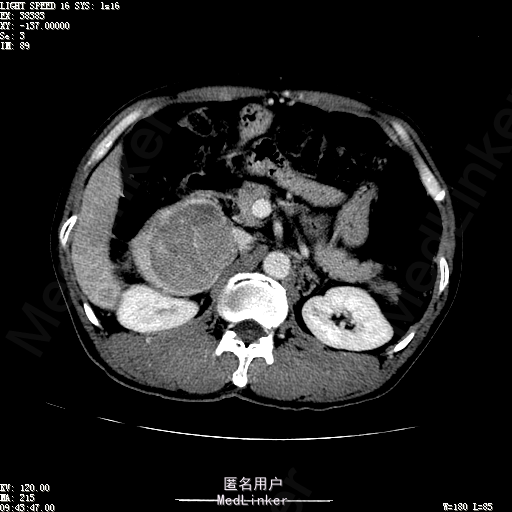

查体:体温36.4℃,脉搏76次/分,呼吸18次/分,血压110/70mmHg。神志清晰,发育正常,营养中等,体位自如,表情安静,慢性病容,检查合作。皮肤粘膜颜色正常,无瘀点、紫癜,有肝掌,无蜘蛛痣,无水肿,毛发的生长与分布正常。浅表淋巴结浅表淋巴结未触及肿大。无巩膜黄染,结膜正常。口唇红润,粘膜正常,舌正常,牙龈正常,扁桃体无肿大,无咽部充血。颈部外形对称,颈静脉正常,肝颈静脉回流征阴性,气管居中。甲状腺正常,无颈部血管杂音。胸部形态正常,呼吸运动平稳规律,无呼吸困难,肋间隙正常。触诊语颤正常,无胸膜摩擦感,肺下界位于右锁骨中线第六肋间。呼吸音正常,未闻及干湿啰音,无胸膜摩擦音。无心前区隆起,心尖搏动正常,心率:76次/分,心律齐,心音正常,无杂音,无心包摩擦音。无大动脉及周围血管征,无奇脉及交替脉,无水冲脉,无枪击音,腹型对称,无腹壁静脉曲张,未见胃肠型及蠕动波,无瘢痕,脐部正常。无压痛,无反跳痛,无腹肌紧张,无腹部包块。肝未触及,Murphy征阴性,脾未触及,肾未触及,无移动性浊音。无肝区叩击痛,无肾区叩击痛,无脾区叩击痛。肠鸣音正常4次/分,无气过水声。外阴及肛门:未查。四肢正常,关节正常,无下肢水肿,无下肢静脉曲张,无杵状指趾。 辅助检查:彩超:肝表面欠光滑,肝内占位5.2*5厘米 ct如下图

诊断:乙肝肝硬化 代偿期 原发性肝癌。 患者病史明确,目前化验转氨酶轻度升高,说明有活动性肝损伤,白蛋白降低提示肝脏合成代谢功能下降,AFP从一年前至今逐渐升高,提示活性肿瘤细胞增多。CT所见明确诊断肝癌,并有周围卫星灶,应近期行TACE治疗。 处置:DSA下肝动脉造影及TACE 手术简要经过:患者平卧位,术区皮肤消毒,铺手术巾,2%利多卡因局麻后,Seldinger法穿刺右股动脉,入血管鞘,5F猪尾管腹主动脉造影,超滑导丝yidao5F RH管腹腔干、肠系膜上动脉、左肾动脉分别造影,腹腔干造影时,见肝右叶7-8处小结节样肿瘤染色,未见外凸生长较大病灶染色。微导管超选肝右动脉注入三氧化二砷碘油混悬液10毫升,横结肠遮挡部位见较大病灶有伞状碘油沉积。复查造影未在见肿瘤染色,拔出导管和血管鞘,穿刺处压迫止血,加压包扎。术毕。

患者术后8天来,无不适,无发热,无腹痛和腹胀,无恶心呕吐,食欲睡眠好,尿便正常。 查体:神志清,巩膜无黄染,心肺听诊无异常,腹软,无压痛,肝脾肋下未触及,移动性浊音阴性,双下肢无浮肿。 复查化验结果:丙氨酸氨基转移酶 116 U/L、天门冬氨酸氨基转移酶 41 U/L、胆碱酯酶 1995 U/L↓、总蛋白 56.3 g/L、白蛋白 25.9 g/L。白细胞计数 5.8 10^9/L、红细胞计数 3.18 10^12/L、血小板计数 175.0 10^9/L、*血红蛋白 83 g/L、血小板分布宽度 15.7 、血小板压积 0.175 %、*红细胞压积 24.6 %、平均红细胞血红蛋白 26.1 pg、平均红细胞血红蛋白浓度 337.0 g/L、平均红细胞体积 77.5 fL、平均血小板体积 10.0 fL、嗜碱性粒细胞百分比 0.4 %、嗜碱性粒细胞数量 0.02 10^9/L、中性粒细胞百分比 70.4 %、中性粒细胞数量 4.10 10^9/L、嗜酸性粒细百分比 2.1 %、嗜酸性粒细胞数量 0.12 10^9/L、单核细胞百分比 12.2 %、单核细胞计数 0.7 10^9/L、淋巴细胞数量百分比 14.9 %、淋巴细胞计数 0.9 10^9/L。甲胎蛋白 23564.00 ng/mL 患者术后第8天开始行FOLFOX6化疗。CT上可见明显碘油沉积,术后甲胎蛋白下降治疗有效。嘱患者术后必须定期复查